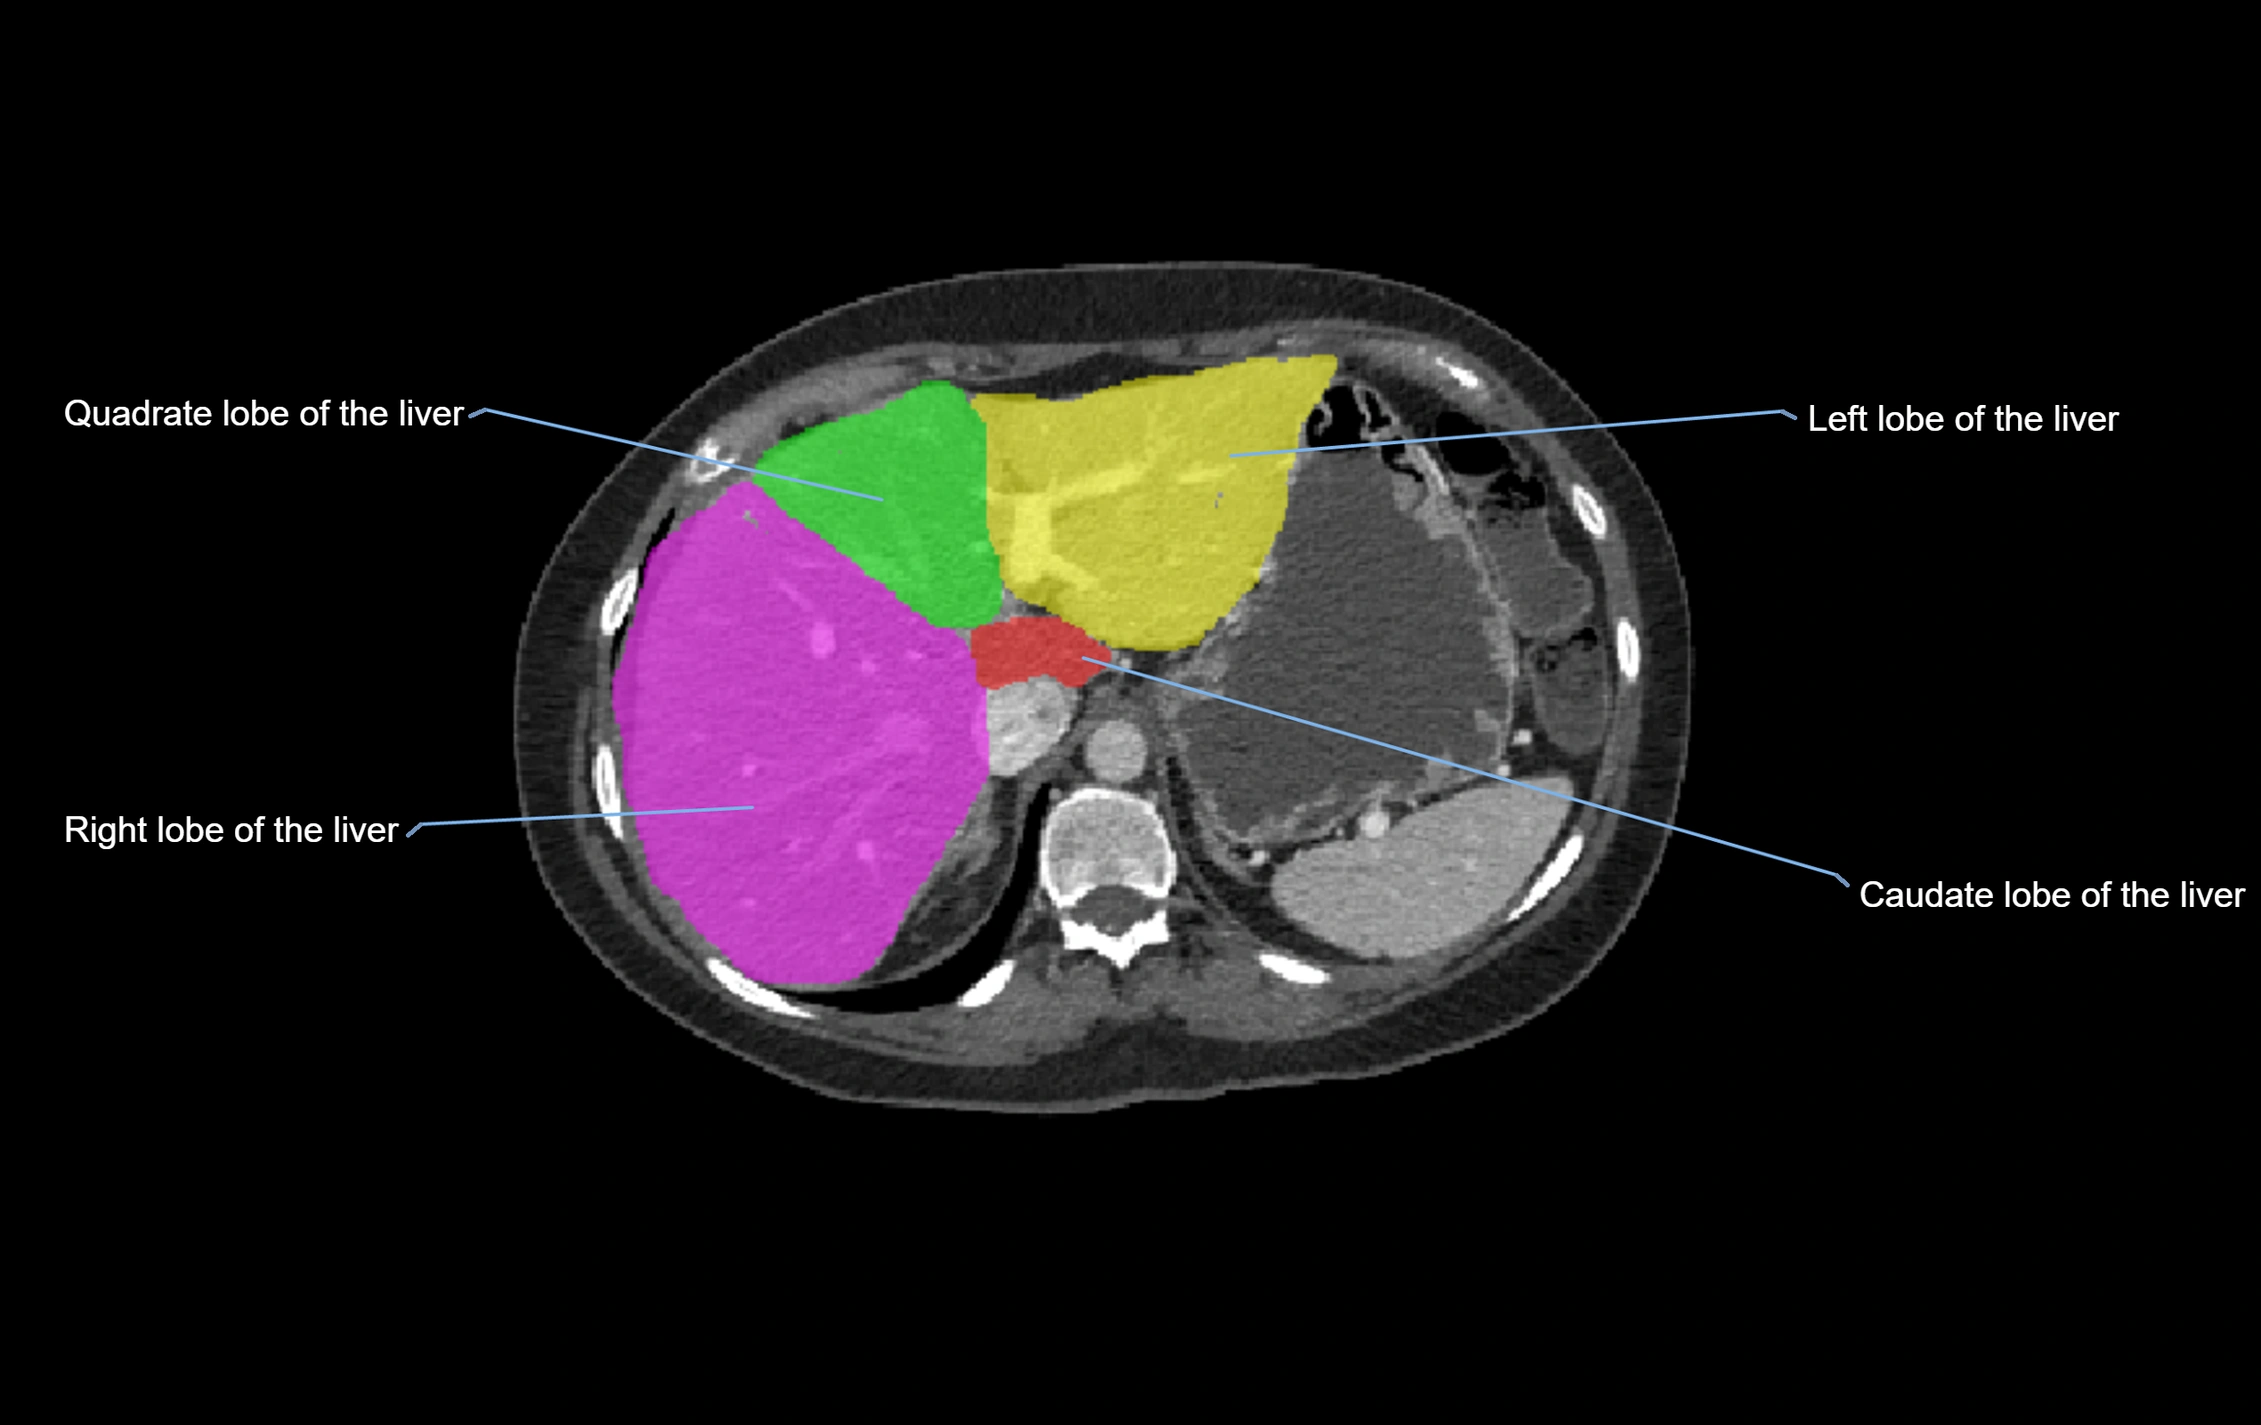

CT Image

image